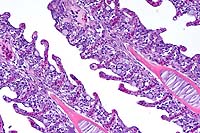

- The lung has multiple, discrete, subpleural granulomas which

each contain a single immature cestode that lacks a bladder wall.

The cestode larvae are nonsegmented and contain an invaginated

scolex. Occasional sections of the larvae show the presence of

suckers in the invaginated canal. Larvae have multiple small

lightly basophilic calcareous corpuscles. The reaction is characterized

by fibrous septal thickening, type II pneumocyte hyperplasia

and a mix of inflammatory cells consisting of eosinophils, macrophages,

plasma cells, and lymphocytes. A layer of degenerate inflammatory

cells lies adjacent to the cestodes. The pleura is thickened

by chronic pleuritis.

- Case 8-1 . Lung. The 2x view shows 3 profiles of cestode

larva surrounded by a dense inflammatory infiltrate forming a

granuloma adjacent to the pleura surface. Surrounding alveoli

have mild alveolar emphysema and thickened alveolar septa. At

40x, multiple calcarious corpuscles (blue bodies with clear halos)

are scattered within the mesenchyme of the larva. The tegument

has a thick eosinophilic, 15-20u, smooth surfaced cuticle. The

surrounding interstitium is fibrotic with moderate numbers of

infiltrating eosinophils and fewer macrophages and lymphocytes.